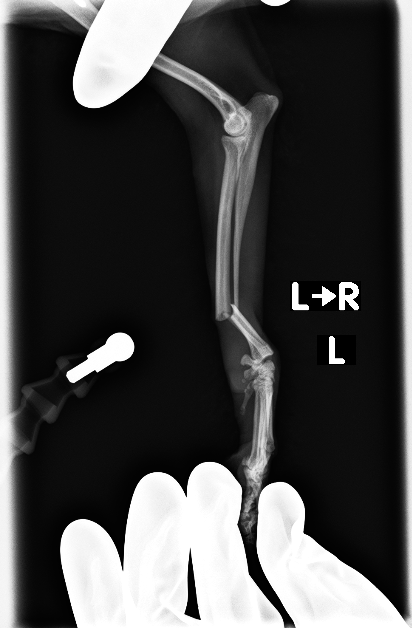

左前肢、橈骨、尺骨骨折

before